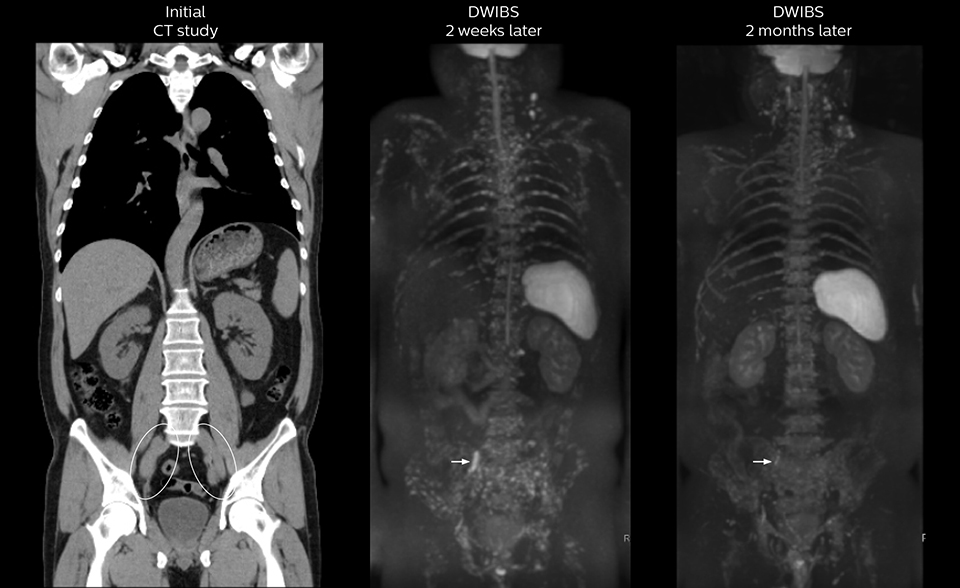

After implementing the improved whole body protocol, the radiology team initially did not see a large increase in referrals, although Dr. Nobusawa saw clinical cases where the DWIBS images provided him valuable information for diagnosis. This is why Dr. Nobusawa and Mr. Naka started to actively educate referring physicians about the value of whole body DWIBS. They organized several presentations for physicians in the hospital, where they explained how DWIBS can be of value in oncology patients. The information it provides can be useful for physicians when staging cancer, as well as when determining or adjusting treatment strategy.

As oncologists and surgeons have learned more about DWIBS, referrals for the exams have increased. In 2015, the 326-bed hospital’s radiology department doubled their number of whole body DWIBS exams compared to 2014.

Mr. Naka remembers some cases where DWIBS provided remarkable information. “In one example, DWIBS visualized bone lesions that could not be seen on PET or SPECT. In another case we had found a bone lesion when a normal L-spine scan for narrowing of the disk space was done. One extra DWIBS scan (2 stations, 8 minutes) demonstrated a lesion that later was confirmed to be the primary region of cancer.”

In certain cases, radiologists now choose DWIBS to make diagnoses that used to depend on nuclear medicine studies. “We don’t have SPECT or PET in our hospital, so for instance for visualizing metastasis and monitoring the effect of treatments such as chemotherapy or radiotherapy, we used to refer patients outside the hospital. Now, these patients are sent to MRI for our whole body protocol with DWIBS,” Mr. Naka says.